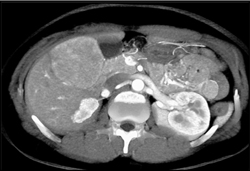

Diagnosis

Hepatoma